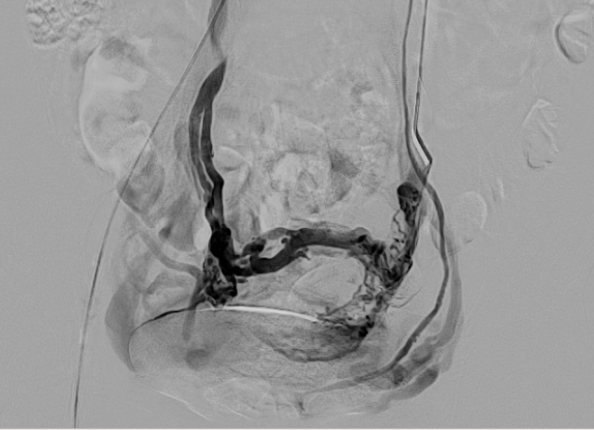

3.经皮导管逆行卵巢静脉造影术

目前认为是盆腔淤血综合征诊断金标准。

盆腔淤血综合征的介入治疗是在局部麻醉状态下,通过股静脉穿刺或颈静脉,引入导丝、导管,插入到盆腔静脉,进行盆腔静脉造影及予以硬化剂、金属弹簧圈等予以栓塞,将有病变扩张的盆腔静脉进行封闭,从而达到治疗的目的。